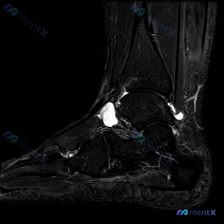

踝关节MRI只看到软组织水肿?这些鉴别点别漏了

刚看到一份踝关节MRI单张图像的分析资料,整理了完整的读片思路给大家参考。

影像基本信息

这是一张踝关节轴位MRI,从信号特征判断属于T2或压脂序列(水呈高信号),核心发现是:

- 距骨骨皮质形态完整,未见明确骨折线,但骨髓腔内信号有异常改变

- 关节周围可见广泛弥漫性高信号,明确提示软组织液体积聚/水肿,边界模糊

- 内踝前方内侧区域明显软组织肿胀,胫前伸肌腱前方皮下也可见水肿

- 外踝腓骨肌腱腱鞘区域也需要关注是否存在腱鞘积液

- 关节间隙周围可见明确液性信号,提示存在关节腔积液